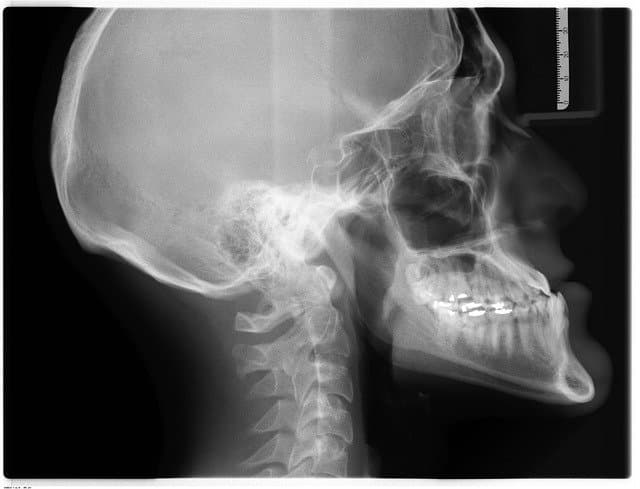

턱관절은 귀 앞, 좌우에 있으며 입을 벌리거나 닫거나 할 때에 움직이는 부분입니다. 머리뼈의 측두골과 아래턱뼈의 관절 돌기에서 턱관절을 이루는 부분인 하악두가 관절 원판을 통해서 구성되어 있는 관절로 매우 복잡한 구조를 하고 있습니다.

턱관절 장애로 의심되는 증상이 나온 경우에는 가급적 빨리 진찰을 받아야 합니다. 진찰은 사전에 턱관절 장애와 관련된 생활 습관에 대한 설문에 응답하는 문진으로 시작됩니다. 그다음에 턱관절과 주변 근육의 촉진, 턱 운동 검사, X레이 촬영을 합니다. 또 필요에 따라서 CT나 MRI 검사, 치아교합 상태를 조사하고 턱관절의 상태, 증상의 원인을 규명합니다.